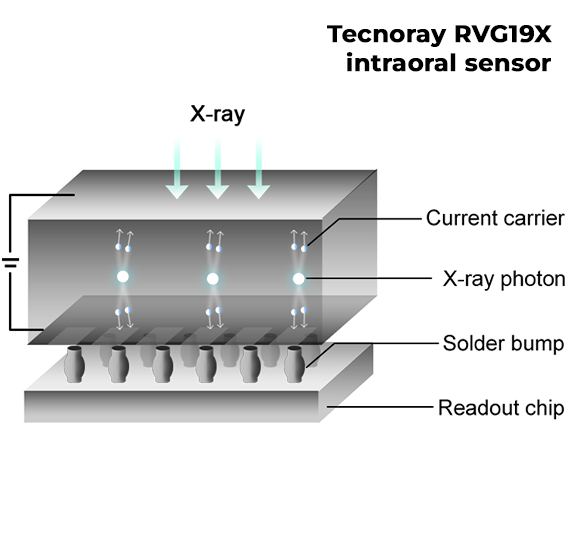

Il sensore intraorale Tecnoray RVG19X introduce in odontoiatria la più recente tecnologia photon-counting, una soluzione avanzata già utilizzata nella diagnostica TC di ultima generazione.

Grazie all’imaging diretto, evita la dispersione luminosa tipica dei sistemi indiretti, garantendo immagini cliniche stabili, nitide e ad altissima qualità.

Il sensore intraorale Tecnoray RVG19X utilizza chip al silicio di ultima generazione, una tecnologia avanzata che sostituisce il tradizionale ioduro di cesio (CsI).

Grazie a questa innovazione, il sensore offre immagini nitide e prive di sfocature, garantendo una diagnosi più precisa e un’esperienza di lavoro più efficiente.

I chip al silicio assicurano inoltre resistenza, affidabilità e lunga durata, mantenendo prestazioni costanti nel tempo anche in condizioni di utilizzo intenso.